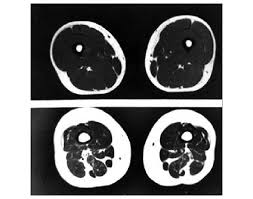

A dor leva ao sedentarismo, que provoca perda de massa muscular (sarcopenia).A imagem abaixo é de uma ressonância magnética que mostra a diferença entre a quantidade de massa muscular em uma pessoa praticante de atividade física (imagem superior) e de uma que não pratica (imagem inferior). A parte mais escura da imagem representa a massa muscular.